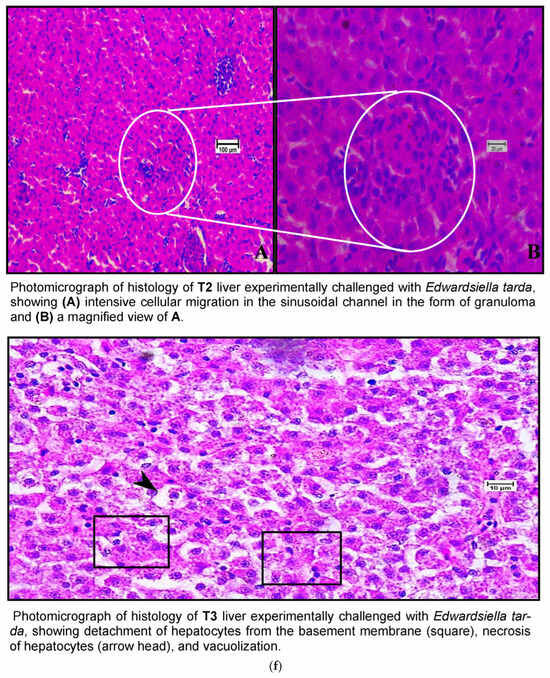

Histological examination of the livers of fish fed the control diet (CT) and the high-dose TABP diet (T3) revealed significant differences in the liver pathology (Figure 7a,b). The livers of fish fed the CT diet had a normal organization of polygonal hepatocytes, normal bile duct, and central vein. In contrast, the livers of fish fed the T3 diet showed fibrosis with fat deposits and altered the normal architecture of the hepatocytes. These findings are consistent with previous studies that have shown that high doses of TABP can cause liver damage in fish. The liver is a vital organ for fish, as it plays a role in digestion, absorption, metabolism, and detoxification. Liver damage can lead to a number of problems, including impaired growth, decreased reproduction, and increased susceptibility to disease. The findings of this study suggest that high doses of TABP can cause liver damage in fish, and further research is needed to determine the safe level of exposure for fish. In addition to the histological changes, the fish fed the T3 diet also had increased levels of oxidative stress markers in the liver. Oxidative stress is a condition that occurs when there is an imbalance between the production of free radicals and the body’s ability to remove them. Free radicals are unstable molecules that can damage cells and tissues. The increased levels of oxidative stress markers in the fish fed the T3 diet suggest that TABP may be causing oxidative stress in the liver, which could contribute to the liver damage observed in this study. The findings of this study provide evidence that high doses of TABP can cause liver damage in fish. Further research is needed to determine the safe level of exposure for fish and to identify the mechanisms by which TABP causes liver damage.

Figure 7.

(a) A photomicrograph of the livers of CT and T1 groups. (b) A photomicrograh of the livers of T2 and T3. (c) A photomicrograph of the livers of CT and T1 groups challenged with A. hydrophila. (d) A photomicrograph of the livers of T2 and T3 groups challenged with A. hydrophila. (e) A photomicrograph of the livers of CT and T1 infected with E. tarda. (f) A photomicrograph of the histology of the liver of T2 and T3 infected with E. tarda.